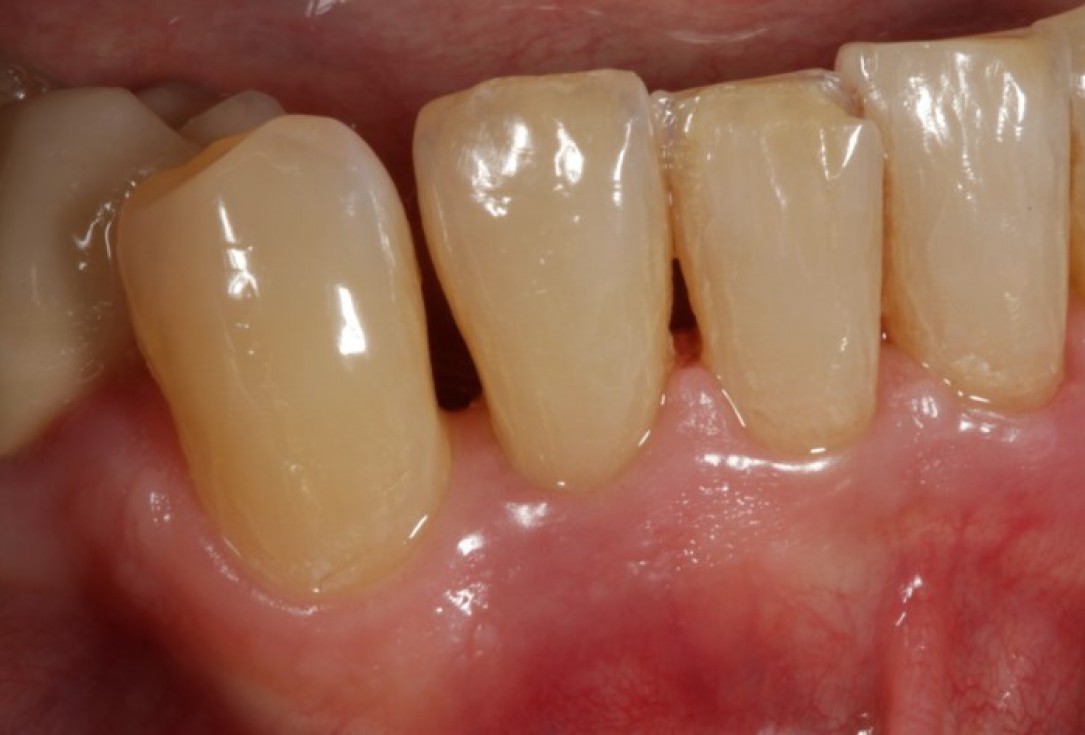

02/08 - Pre-surgical probing reveals a deep intrabony defect on the distal aspect of tooth 42.

Non-contained intrabony defect treated using Straumann® Emdogain® and a synthetic bone grafting material - Prof. Dr. Dr. A. Kasaj